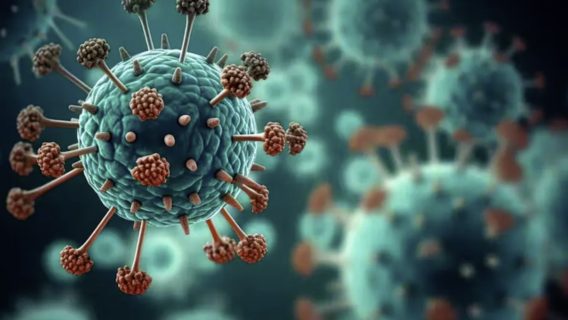

В Україні 13 людей захворіли на китайський метапневмовірус (HMPV). Наскільки він небезпечний, чи може стати новою пандемією, як уберегтися від хвороби. Розбір

В Україні 13 людей захворіли на китайський метапневмовірус (HMPV). Наскільки він небезпечний, чи може стати новою пандемією, як уберегтися від хвороби. Розбір

У Китаї та світі шириться метапневмовірус людини (HMPV). За даними Центру громадського здоров’я, протягом епідемічного сезону в Україні вже 13 людей захворіли на HMPV. Хоча це не новий вірус, а його симптоми подібні до застуди, ми пояснюємо, наскільки він небезпечний, симптоми метапневмовірусу, чи може він стати новою пандемією та як захистити себе від HMPV.